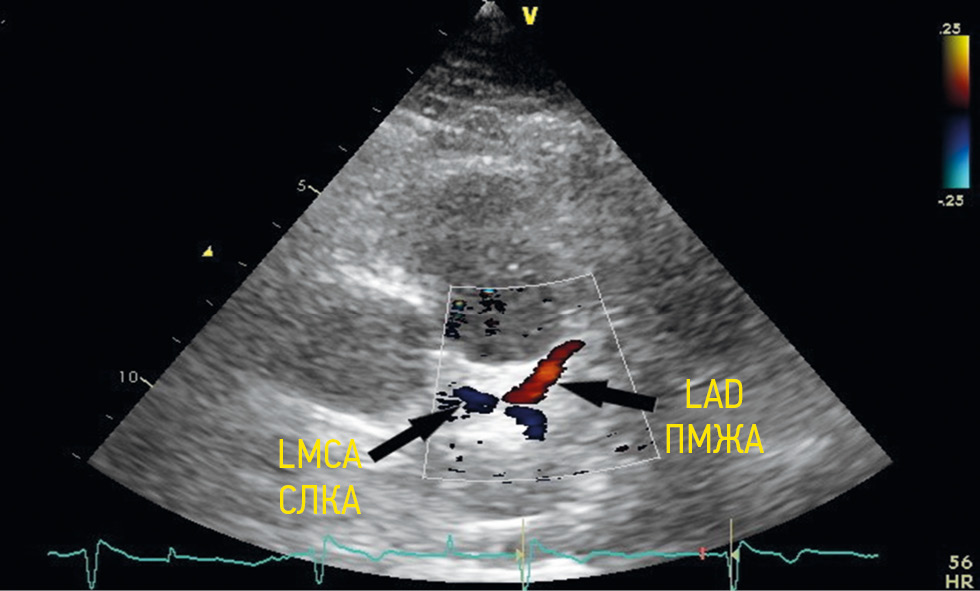

To visualize the left coronary artery trunk, a normal antegrade blood flow in red or blue (red was detected by flow directed to the transducer, and blue was from the transducer) was determined using color Doppler imaging in the area of the left coronary sinus depending on anatomical features of the chest, transducer position, and left coronary artery origin (Figure 1).

Fig. 1. Vizualization of the left main coronary artery from a modified left parasternal position along the long axis. LMCA — left main coronary artery; LAD — left anterior descending artery / Рис. 1. Визуализация ствола левой коронарной артерии из модифицированной левой парастернальной позиции по длинной оси. СЛКА — ствол левой коронарной артерии; ПМЖА — передняя межжелудочковая артерия